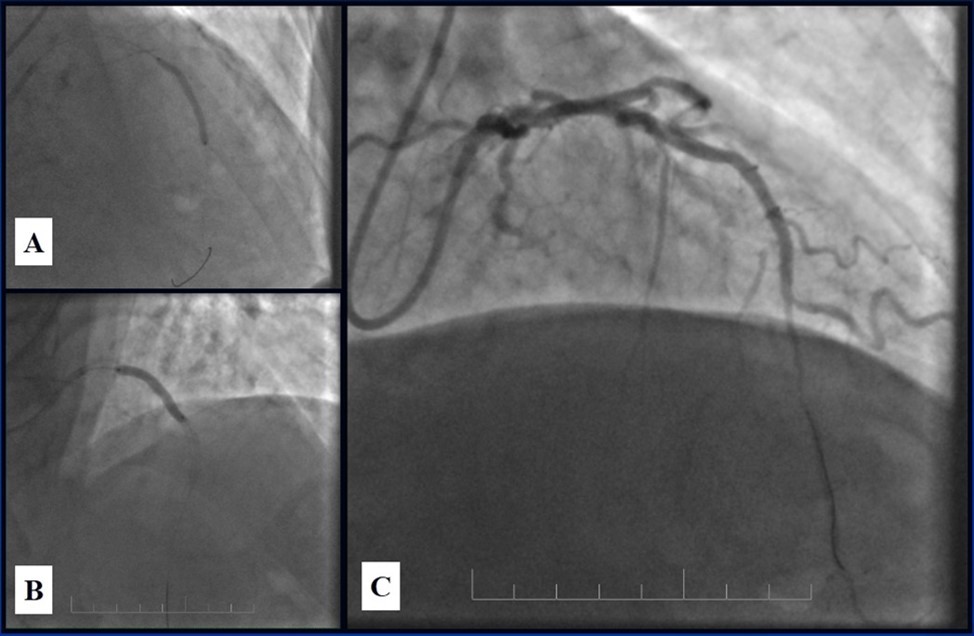

In the first stage, despite the fact that BMS is contraindicated in diabetic patients, RCA was stented with 3 bare-metal stents (BMS) (Rebel, Boston Scientific) (due to financial problems - drug-eluting stents was not covered by insurance). We used BMS to have at least temporarily patent RCA during LMCA stenting (Figure 5) (we believe that, when RCA is functional, LMCA stenting is safer). LAD was stented with 2 drug-eluting stents (Resolute Integrity, Medtronic). After the first PCI patient’s symptoms were relieved (Figure 6).

Figure 6.A, B - Stenting of the LAD with DES; C - Angiography result.

A, B - Stenting of the LAD with DES; C - Angiography result.

Due to financial problems the second stage was performed after 3 months (during this time the patient solved his financial problems). CAG revealed patent stents in LAD (Figure 7), and 60-70% restenosis by BMS in RCA (Figure 8). In-stent restenosis was treated by plain old balloon angioplasty (POBA), the optimal result was obtained (Figure 9). After LMCA quadrifurcation balloon predilation, 2.5×26 mm DES (Resolute Integrity, Medtronic) was implanted in the IMA, using a modified balloon mini-crush technique. The stent was minimally protruded in the LMCA and its edge was crushed by preloaded MB balloon. Next 2.5×30 mm DES (Resolute Integrity, Medtronic) was implanted in OM1 through the CX (first marginal and circumflex arteries in this particular case have the same ostium). The stent was protruded in the LMCA as in conventional modified balloon crush stenting technique, after stent deployment, its balloon was pulled back and overinflated, then protruded stent was crushed by preloaded MB balloon (Figure 10). 3.5×15 mm DES was implanted in the LMCA so that distal part of the stent covered ostial and proximal segments of the LAD. Sequential post-dilatations were performed using a kissing balloon technique (1. LMCA-LAD-IMA,2. LMCA-LAD-CX-1OM). After post-dilatations, through the stent implanted in CX-OM1, coronary wire and smaller diameter balloon (2.0 mm) were advanced in direction of the CX mid-segment and by balloon dilatation stent’s strut was opened (provisional stenting technique for CX). Finally, the proximal optimization technique was performed in the LMCA using a 3.5 mm diameter non-compliant balloon (Figure 11). The final angiographic image was good, the intervention ended without complications (Figure 11, Figure 12). We could not confirm the result with IVUS or OCT due to several technical and financial problems (not covered by insurance). 1 month after PCI, at regular checkout, the ejection fraction was 48%, the functional class of the Congestive Heart Failure decreased from class II-III to class I and the patient complaints have been disappeared.

Figure 7.Patent stents in LAD; A – AP-cranial 30° projection, B – Right anterior oblique 20°/caudal 20° projection.

Patent stents in LAD; A – AP-cranial 30° projection, B – Right anterior oblique 20°/caudal 20° projection.